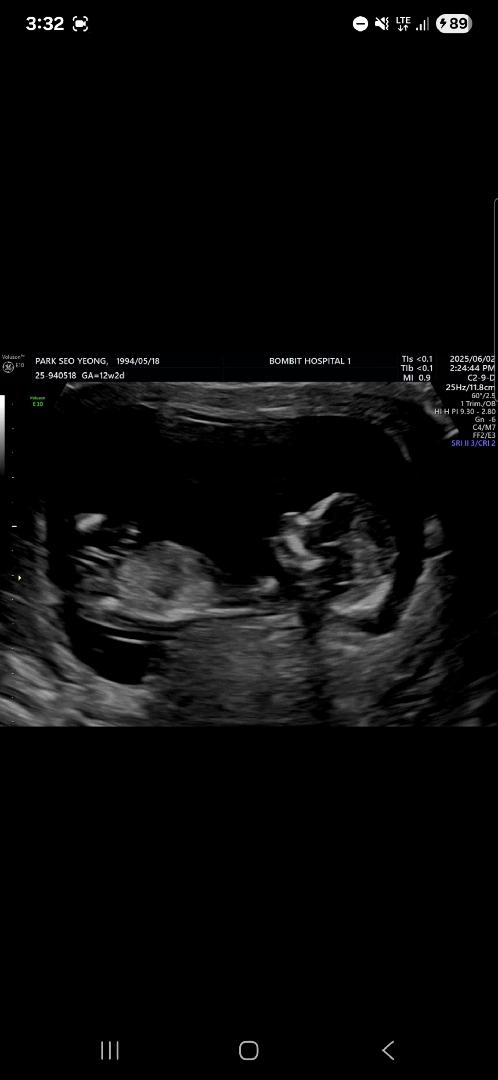

다른 사진으로 다시 올려요! 12주 2일입니다

허벅지뼈같다고 하셔서 다른사진도 올려봐요 지피티는 딸 같다던데.. 궁금합니다 하루종일 댓글 달리나 보고있어요 ㅠ

돌기가 살짝 솟은 것 같아요! 아들 예상해봅니다!

끝이갈라지면 딸이래요~